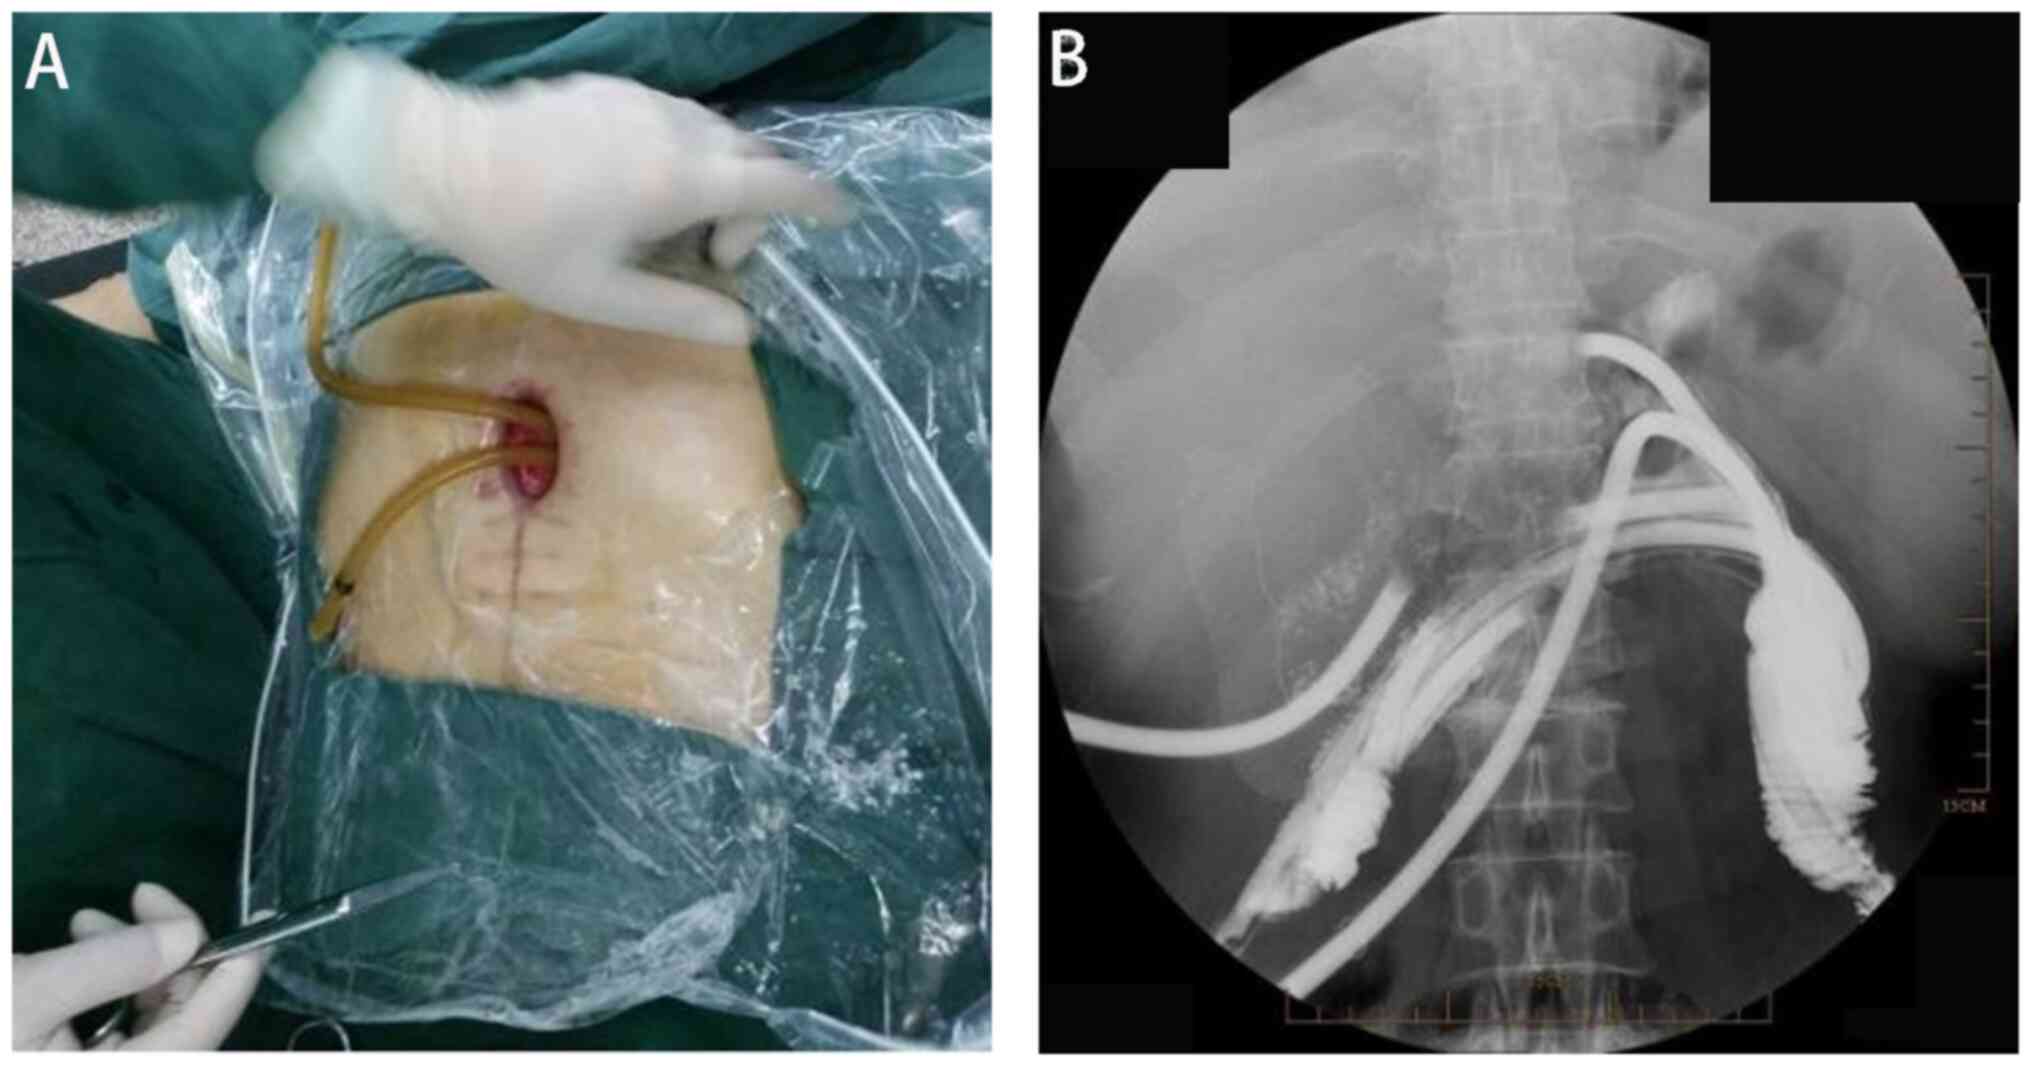

The second stage of treatment involved colon catheterization for external drainage (5 weeks after admission). The patient was placed in the supine position without anesthesia and underwent an endoscopy through an upper abdominal incision opening under direct vision. Use of the same transurethral prostate resection instruments for visualization revealed residual titanium nails and necrotic tissue at the colonic fistula site. The anterior wall of the colon anastomosis had ruptured by ~1/3 of its circumference. Proximal and distal ends of the colon were identified, and external drainage was established using an F24 porous rubber tube inserted with guidewire guidance (Fig. 2). The tubes were rinsed daily with physiological saline solution. After 1 week, the intestinal flushing solution was clear, and the granulation tissue at the abdominal opening was red and moist, without purulent secretions.

Figure 2

Insertion of the intestinal drainage tube. (A) Drainage tube was inserted from the intestinal skin fistula. (B) Radiographic examination of the drainage tube.